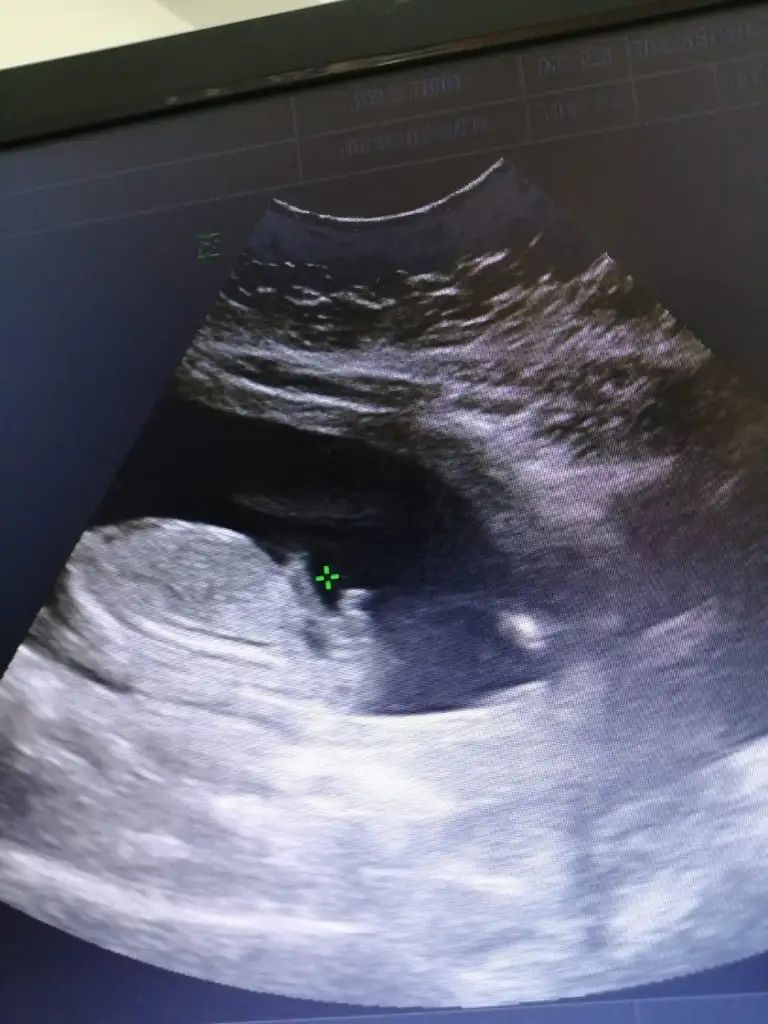

Merhaba kızlar bende temmuz annesi olacağım nasip olursa şuan 17+2 haftalik gebeyim ve tüp bebekle gebe kaldim. Doktorum bana 12. Haftada erkeğe benziyor dedi dün kontrolde ters duruyor çok zor görmek ama kız bu bebek dedi. Bende ikilem yaşamaktansa dün özel bir muayenehanesi olan bir doktor var yüksek kalite ultrason cihazlarla bakıyor ve ayrıntılı bakıyor bebeğin damarlarına kadar görüyor ona gittik. Ama cinsiyetle ilgili hicbirsey sormadık o herseyine baktıktan sonra biliyorsunuzdur heralde bebeğiniz erkek dedi ben tekrar şok dedim kız bebek dediler bize dedim doktor güldü hayır kesin erkek dedi ve testislerini ve pipisini gösterdi. Şimdi ben tekrar gittiğimde farklı birsey söylenecek diye stres içindeyim bebeğime bir zibin almak istedim onu bile alamadım dün. Cinsiyetin fotosunda ekliyorum kızlar çok zormuş bu durum

erkek e benziyor gerçi ben pek anlamam ama ayrıntılı da bakmışlar sonuçta bence çok yanılmaz olmaz bu saatten sonra:)